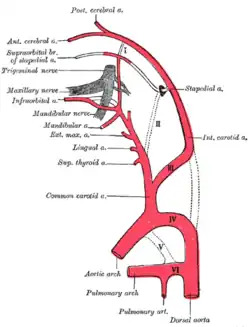

Embryonal entstehen zunächst die paarige Aorta dorsalis und die ebenfalls paarige Aorta ventralis, die durch sechs Kiemenbogenarterien miteinander verbunden sind. In der weiteren Entwicklung werden einzelne Gefäßabschnitte zurückgebildet, andere verstärken sich deutlich. So bildet die linke vierte Kiemenbogenarterie den Aortenbogen, die ventrale Aorta zwischen dritter und vierter Kiemenbogenarterie die Arteria carotis communis, weiter rostal die Arteria carotis externa und ihre Äste. Die dritte Kiemenbogenarterie wird zum ersten Abschnitt der Arteria carotis interna, die sich in der dorsalen Aorta fortsetzt. Der Abschnitt der Aorta dorsalis zwischen dritter und vierter Kiemenbogenarterie hingegen wird zurückgebildet (siehe nebenstehende Abbildung). Die primitive Arteria carotis interna teilt sich an der Anlage des späteren Gehirns in einen kranialen und einen kaudalen Ast. Ersterer bildet zunächst um die 4. Embryonalwoche die Arteria cerebri anterior und die Arteria choroidea anterior, erst um die 9. Woche entsteht aus einem von mehreren Seitenästen die später viel stärkere Arteria cerebri media. Der kaudale Ast entsendet segmentale Arterien zum Neuralrohr, aus denen sich unter anderem die Kleinhirnarterien ableiten. Um die 7. Embryonalwoche entsteht aus diesem Ast auch die Arteria cerebri posterior. Etwa um dieselbe Zeit verschmelzen die beiden Abschnitte des kaudalen Astes vor dem Hirnstamm und bilden die unpaare Arteria basilaris. Die Wirbelarterien bilden sich aus der Fusion von kleineren longitudinalen (in Körperlängsrichtung liegenden) Anastomosen zwischen den primitiven segmentalen Arterien der Halsregion. Sie gewinnen eine Verbindung zu der frühen Arteria basilaris. Um die 9. Woche kehrt sich die Flussrichtung in der Basilararterie bis zur Höhe der Arteria cerebri posterior um, so dass sie mit allen Tochtergefäßen nun hämodynamisch zur hinteren Strombahn gehört. Ganz zuletzt bildet sich die Arteria communicans anterior durch partielle Fusion der Arteriae cerebri anteriores.